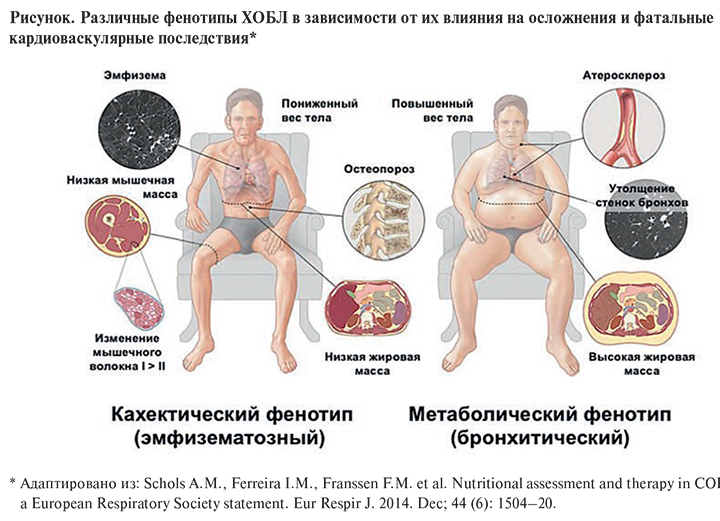

Роль легких в метаболических процессах